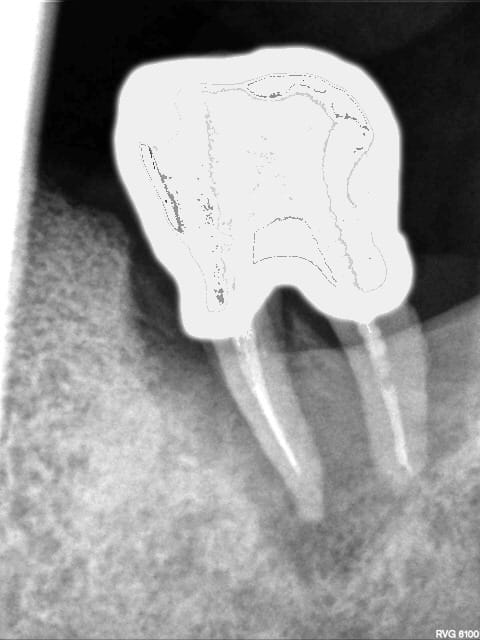

R 69 = 11/05/2013

R69 aqhkjh - Eugenol

R71 est de cette semaine, allez y comprendre quelque chose, dame nature a été très gentille sur ce coup là, de l'os s'est reformé.

R71 yby2cf - Eugenol

Index vakr2r - Eugenol

L'angulation est différente, et pour preuve sur la R71 on voit bien les deux canaux mésiaux de manière distincte, alors qu'ils étaient toujours confondus sur les autres radio...

Il n'y a jamais de "miracle" en paro! Pour une lésion endo oui, mais pas pour une lésion paro...